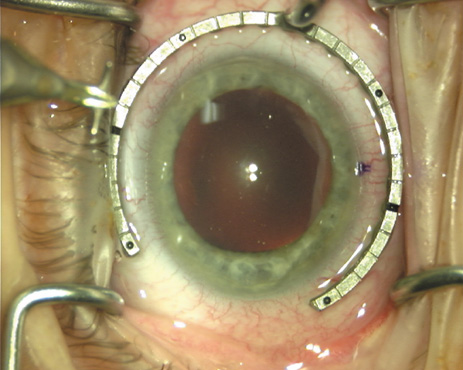

Case 1 is a 68-year-old male who presented for right cataract surgery. His refraction was −1.00 +2.25 × 80 and was recorded as reliable, consistent with his modest cataract density. Keratometry readings were 44.75 × 75 and 43.00 × 165. Corneal topography confirmed slightly more than 2.00 D of regular and slightly oblique cylinder. Consulting the nomogram, a plan was devised for a pair of LRIs to be centered over the 75-degree axis, with each incision delineating 45 degrees of arc. A single plane phaco incision was used and maintained at a size of less than 3.2 mm (Figs. 811).

Fig. 8. Steep meridian is confirmed intraoperatively by keratoscopy. In this left eye viewed from the temporal side, the “short axis” of the corneal mire is seen to be at the 75-degree meridian. (Reprinted from Hardten DR, Lindstrom RL, Davis EA. Phakic Intraocular Lenses: Principles and Practice. Thorofare, NJ: SLACK Incorporated, 2004, with permission.)

Fig. 9. The broad hash marks of the fixation ring/gauge are centered over the 75-degree meridian, using the 6:00 limbal mark for orientation. Alternatively, a Mendez gauge may be used. (Reprinted from Hardten DR, Lindstrom RL, Davis EA. Phakic Intraocular Lenses: Principles and Practice. Thorofare, NJ: SLACK Incorporated, 2004, with permission.)